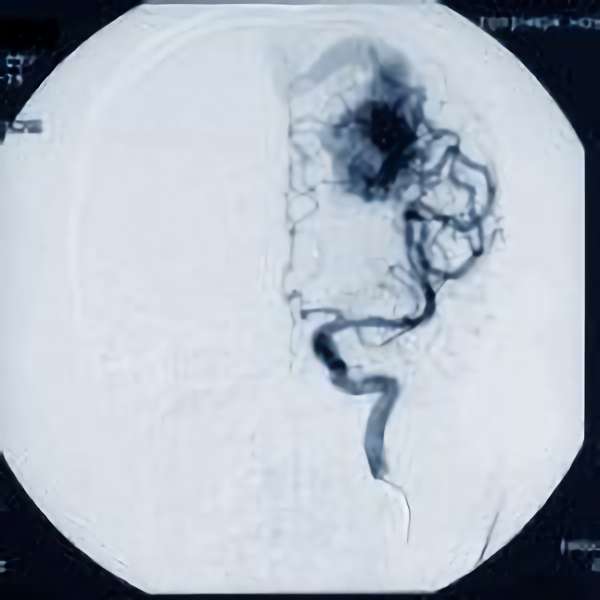

'19年5月

30代

富永/久貝

右中小脳脚 出血再発

SM 3(S1,E1,V1)

米国の病院

No.359 モニタリング

No.359 手術前

No.359 手術中

No.359 手術後

出血既往があり。2回の手術前血管内手術の後に、

Lateral transpeduncular approachにより再々出血予防を目的に

摘出手術を行う。完全摘出であることを確認した。

手術による合併症や後遺症なしで退院した。経過良好。